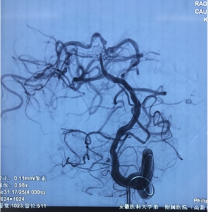

直升机返回高新院区后,早已就位的神经外科、急诊科医务人员迅速开通绿色通道,积极完善术前相关检查及术前准备。并于当日在麻醉科、影像科介入导管室及急诊ICU等多学科协作下,急诊全麻下行全脑血管造影及颅内动脉瘤栓塞术。

由于该患者系基底动脉远端分叶状动脉瘤,位置特殊,形态复杂,累及多根重要血管。神经外科脑血管病团队,仔细分析病情后,采用支架辅助及双微导管技术,成功对该动脉瘤实施了致密栓塞,杜绝了动脉瘤再次破裂出血的风险。